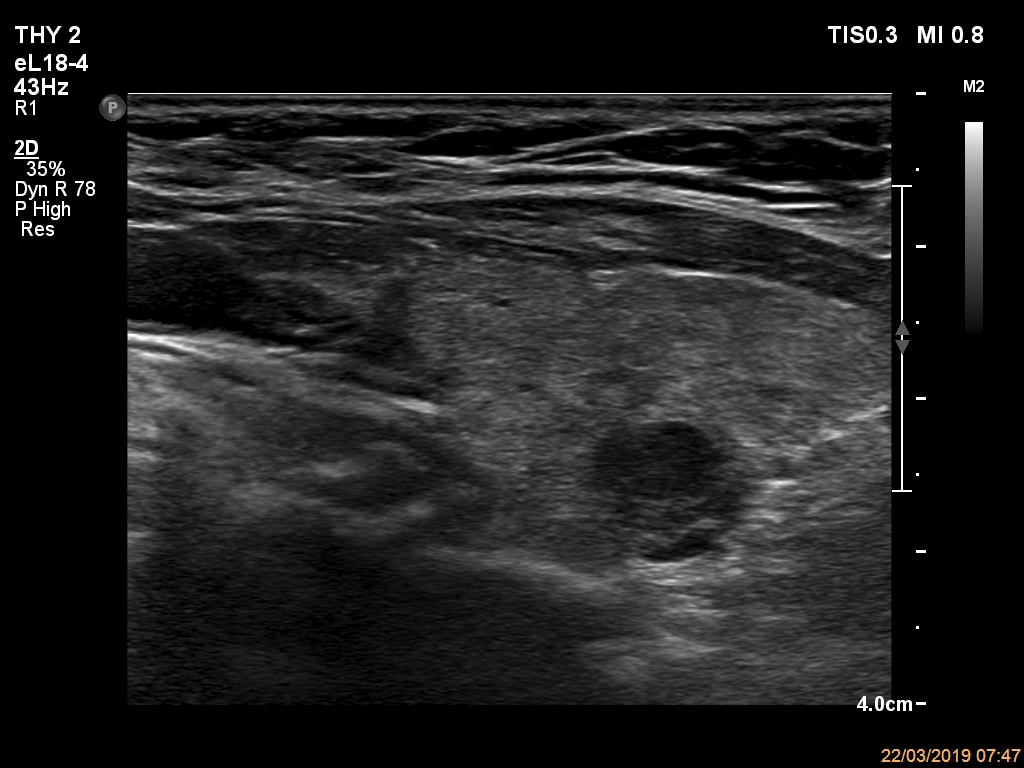

Ultrasonography. The thyroid was echonormal and had multiple nodules. The only lesion of a possible oncological importance was in the left lobe. It was hypoechoic. The dimensions were 16x14x23 mm (width, depth, length, respectively). The lower border presented an undulation which was caused by another, hyperechoic nodule. The nodule presented a predominant perinodular blood flow and had an average rigidity on elastography.

The nodule in the left lobe illustrates non-pathological form of lobulated margins.